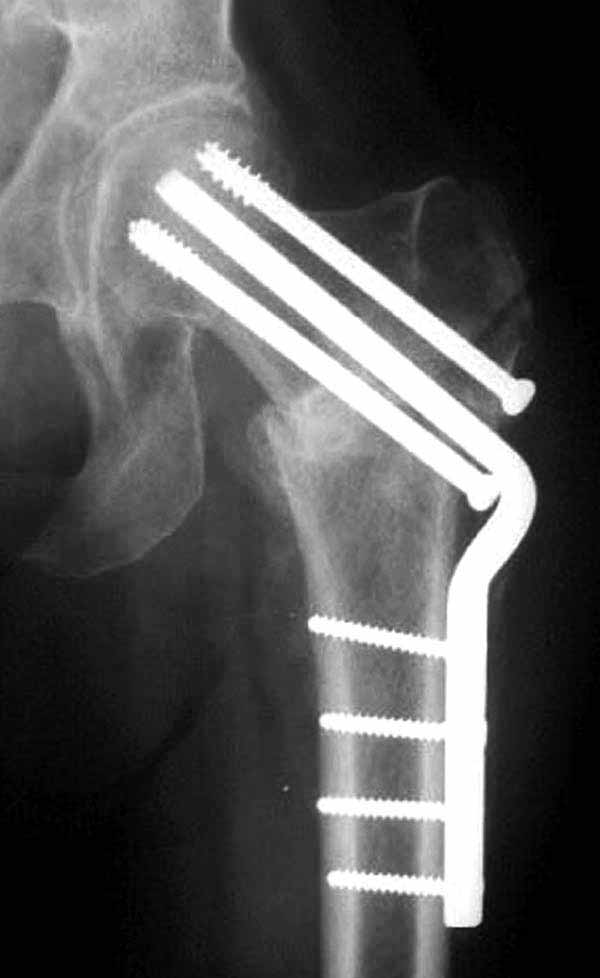

Пациентка Ш. 76 лет, 11 дней назад прооперирована по поводу вколоченного субкапитального перелома шейки левой бедренной кости, 3-мя канюлированными винтами. Вчера пациентка упала в палате. И вот результат- подимплантатный подвертельный перелом левой бедренной кости. Уважаемые коллеги, пожалуйста посоветуйте какой метод дальнейшего лечения предпринять дальше.Соматически пациента повышенного питания, страдает варикозной болезнью нижних конечностей.Из предложенных вариантов коллег - целллокастовая укороченная кокситная повязка, скелетное вытяжение сроком на 40-45 суток - отпали сразу, так как необходимо активизация пациентки.На данный момент рассматриваем следующие варианта реостеосинтеза:(наличие технических возможностей) 1. Длинная Gamma 3 Stryker (с предварительной интраоперационной фиксацией головки спицами).2. Трохантерный штифт DePuy с 2-мя метафизарными винтами в проксимальном отделе, (также с интраоперационной фиксацией головки спицами. Очень настораживает стабильность фиксации с проксимальном отделе с связи с выборкой костной ткани ранее находящимися там канюлированными винтами. Сейчас пациентка находится на скелетном вытяжении, с дисциплинирующим грузом. Операция планируется после праздников. Заранее извиняемся за качество и неполное соответствие проекций на R-ммах (R-служба отдельная песня). При интраоперационном ЭОП-контроле винты в аксиальной проекции разнесены по шейке.

Перелом, как мне кажется, "чрезимплантный." Мы бы убрали два нижних винта, верхний не трогали (для ротационной стабильности в последующем)+ поставили-бы DHS. Направляющую спицу для шеечного винта вводите до удаления нижних и тогда потеря головкой девственности не будет иметь такого значения.

3. Чем фиксировать: я бы выбрал второй вариант

Согласен с Николаем, винты распоожены так, чтобы эту "мину" заложить. И два внизу, и не должны, даже если один он там, они входить ниже уровня малого вертела, это резко повышает риск подвертельного перелома. Что до остеосинтеза - учитывая 76 лет, более подходящей представляется большего диаметра винт в шейке, то есть гамма.

У больных с ожирением и соматическими заболеваниями нежелательно открывать место перелома. Гвозди от DePuy с двумя шурупами рассчитаны для переломов бедра, и приходилось их применить для фиксации подвертельных переломов, но более адекватную фиксацию создает Gamma 3.

Здесь подобный случай, где стрессовый перелом обнаружен через 2 недели после фиксации. Применен Blade Plate с дополнительными шурупами.